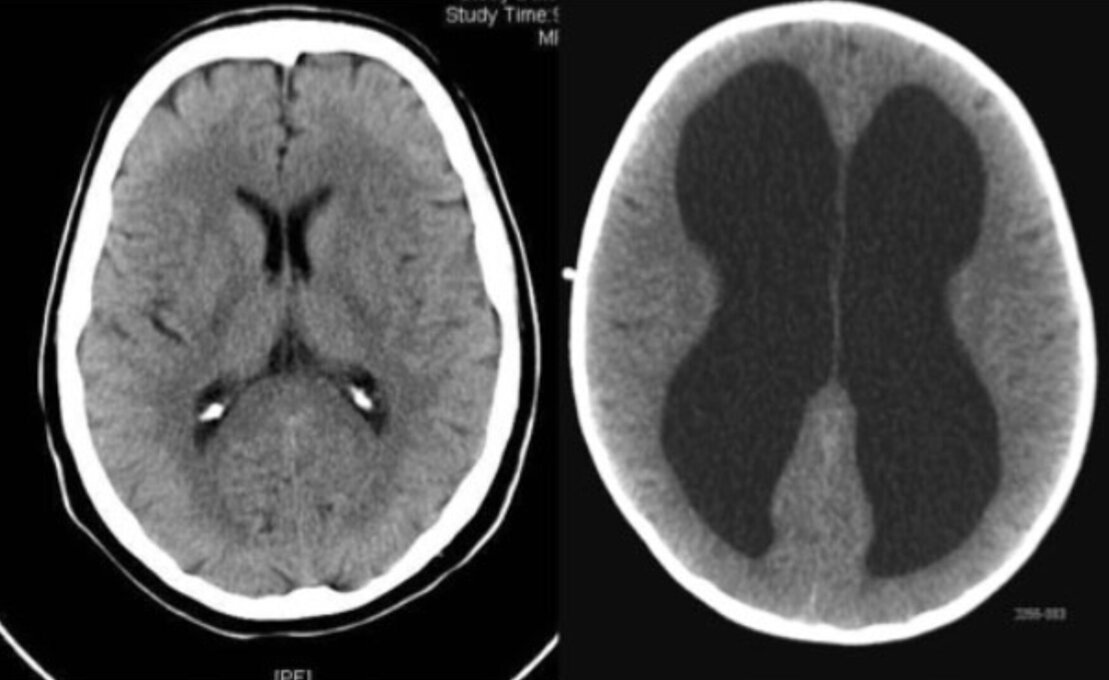

Der sog. Hydrocephalus („Wasserkopf“) ist eine Erkrankung, die praktisch in jedem Lebensalter auftreten kann. Hierbei kommt es zu einer Störung des Hirnwasserkreislaufs. Die Folge ist eine Aufweitung der inneren Hirnwasserkammern (siehe Abbildung).

Je nach Ursache der Erkrankung geht diese Hirnkammererweiterung mit einer mehr oder minder ausgeprägten Erhöhung des Hirndrucks und einem Untergang von Hirngewebe einher.

Links: Darstellung der deutlich erweiterten Seitenventrikel. Rechts: Darstellung der Aquäduktstenose.